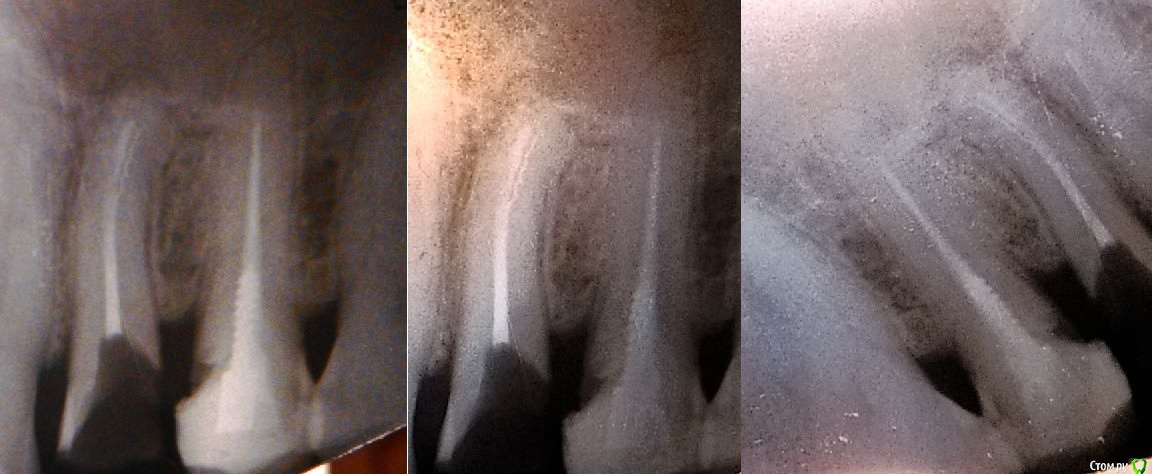

Максим-50 Опубликовано 22 марта, 2015 Поделиться Опубликовано 22 марта, 2015 Здравствуйте.У меня сильно разрушенный верхний 4-ый зуб после неоднократного кариеса и пломбирования, в последнее посещение стоматолога-терапевта врач сначала сказала, что целесообразно только удаление, ставить коронку на этот зуб нет смысла, т.к. через год-два всё равно всё выпадет. Потом решили посмотреть, имеет ли смысл лечить, сделали прицельный снимок, и врач сказала, что в канале зуба виден обломок инструмента, направила для консультации к ортопеду, который направил обратно к терапевту для подготовки под ВКВ. Посоветовал ставить две коронки сразу (на 5 зуб тоже, на котором пломба занимает 2/3), но можно и по отдельности. Для "очистки совести" я обратился в другую клинику, и там ортопед посоветовал поставить штифт+коронку, срок жизни обозначил в те же два-три года, потом будет расцементировка - т.к. с одной стороны (зуба?) стенки вообще нет, наплыв десны на корень и сам корень уже затронут кариесом. Я спросил, а что он думает по поводу обломка инструмента, согласно словам предыдущего специалиста, он ответил, что по его мнению, это штифт, как и в соседнем 5-ом зубе.у меня в связи с этим несколько вопросов:1) кто из них был прав (штифт ли это или всё-таки остаток инструмента)? И если это штифт, то зуб уже должен был быть мёртвым и не болеть вообще, или я не прав?2) насколько это вообще принципиально в плане дальнейших действий?3) если делать на 2-3 года, то потом всё равно надо будет удалять?4) поскольку на соседнем 5-ом зубе большая пломба, плюс разрушен корень на 4-ом то он предложил сделать общую коронку (для большей прочности всей конструкции?), соответственно что надо будет через 2 года с 5-ым зубом, просто поставить одну отдельную коронку на него? Заранее благодарю за ответ.Снимок прилагаю. Ссылка на комментарий

krokomot Опубликовано 22 марта, 2015 Поделиться Опубликовано 22 марта, 2015 1. снимок очень темный, не видно кость около верхушек корней 5 и 4, в 4 есть остаток инструмента и возможно серебрянный штифт (можно определить только клинически)2. принципиально состояние костных тканей около верхушек обсуждаемых зубов3. если состояние тканей корня 4-и удовлетворительное возможно его востановление вкв и коронкой4. зуб 5 лечить вкв и коронкаПо поводу прогноза все зависит от многих факоторов( гигиены, сосояния полости рта в целом, качества плобировки каналов и качества констукции и т.д)Нужен хороший снимок! ( либо переделать, либо правильно сфотографировать имеющийся) Ссылка на комментарий

Максим-50 Опубликовано 23 марта, 2015 Автор Поделиться Опубликовано 23 марта, 2015 2. принципиально состояние костных тканей около верхушек обсуждаемых зубов3. если состояние тканей корня 4-и удовлетворительное возможно его востановление вкв и коронкой4. зуб 5 лечить вкв и коронкаПо поводу прогноза все зависит от многих факоторов( гигиены, сосояния полости рта в целом, качества плобировки каналов и качества констукции и т.д)Нужен хороший снимок! ( либо переделать, либо правильно сфотографировать имеющийся) про 4-ый врач, после того как начала лечить кариес, сказала: "на удивление зуб крепкий", после чего направила к ортопеду. Переснятый снимок: Ссылка на комментарий